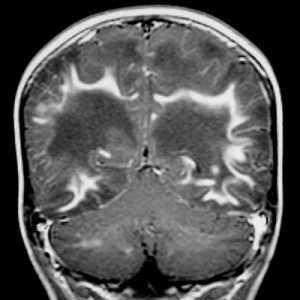

Esclerose Múltipla

deficiencia esclerose